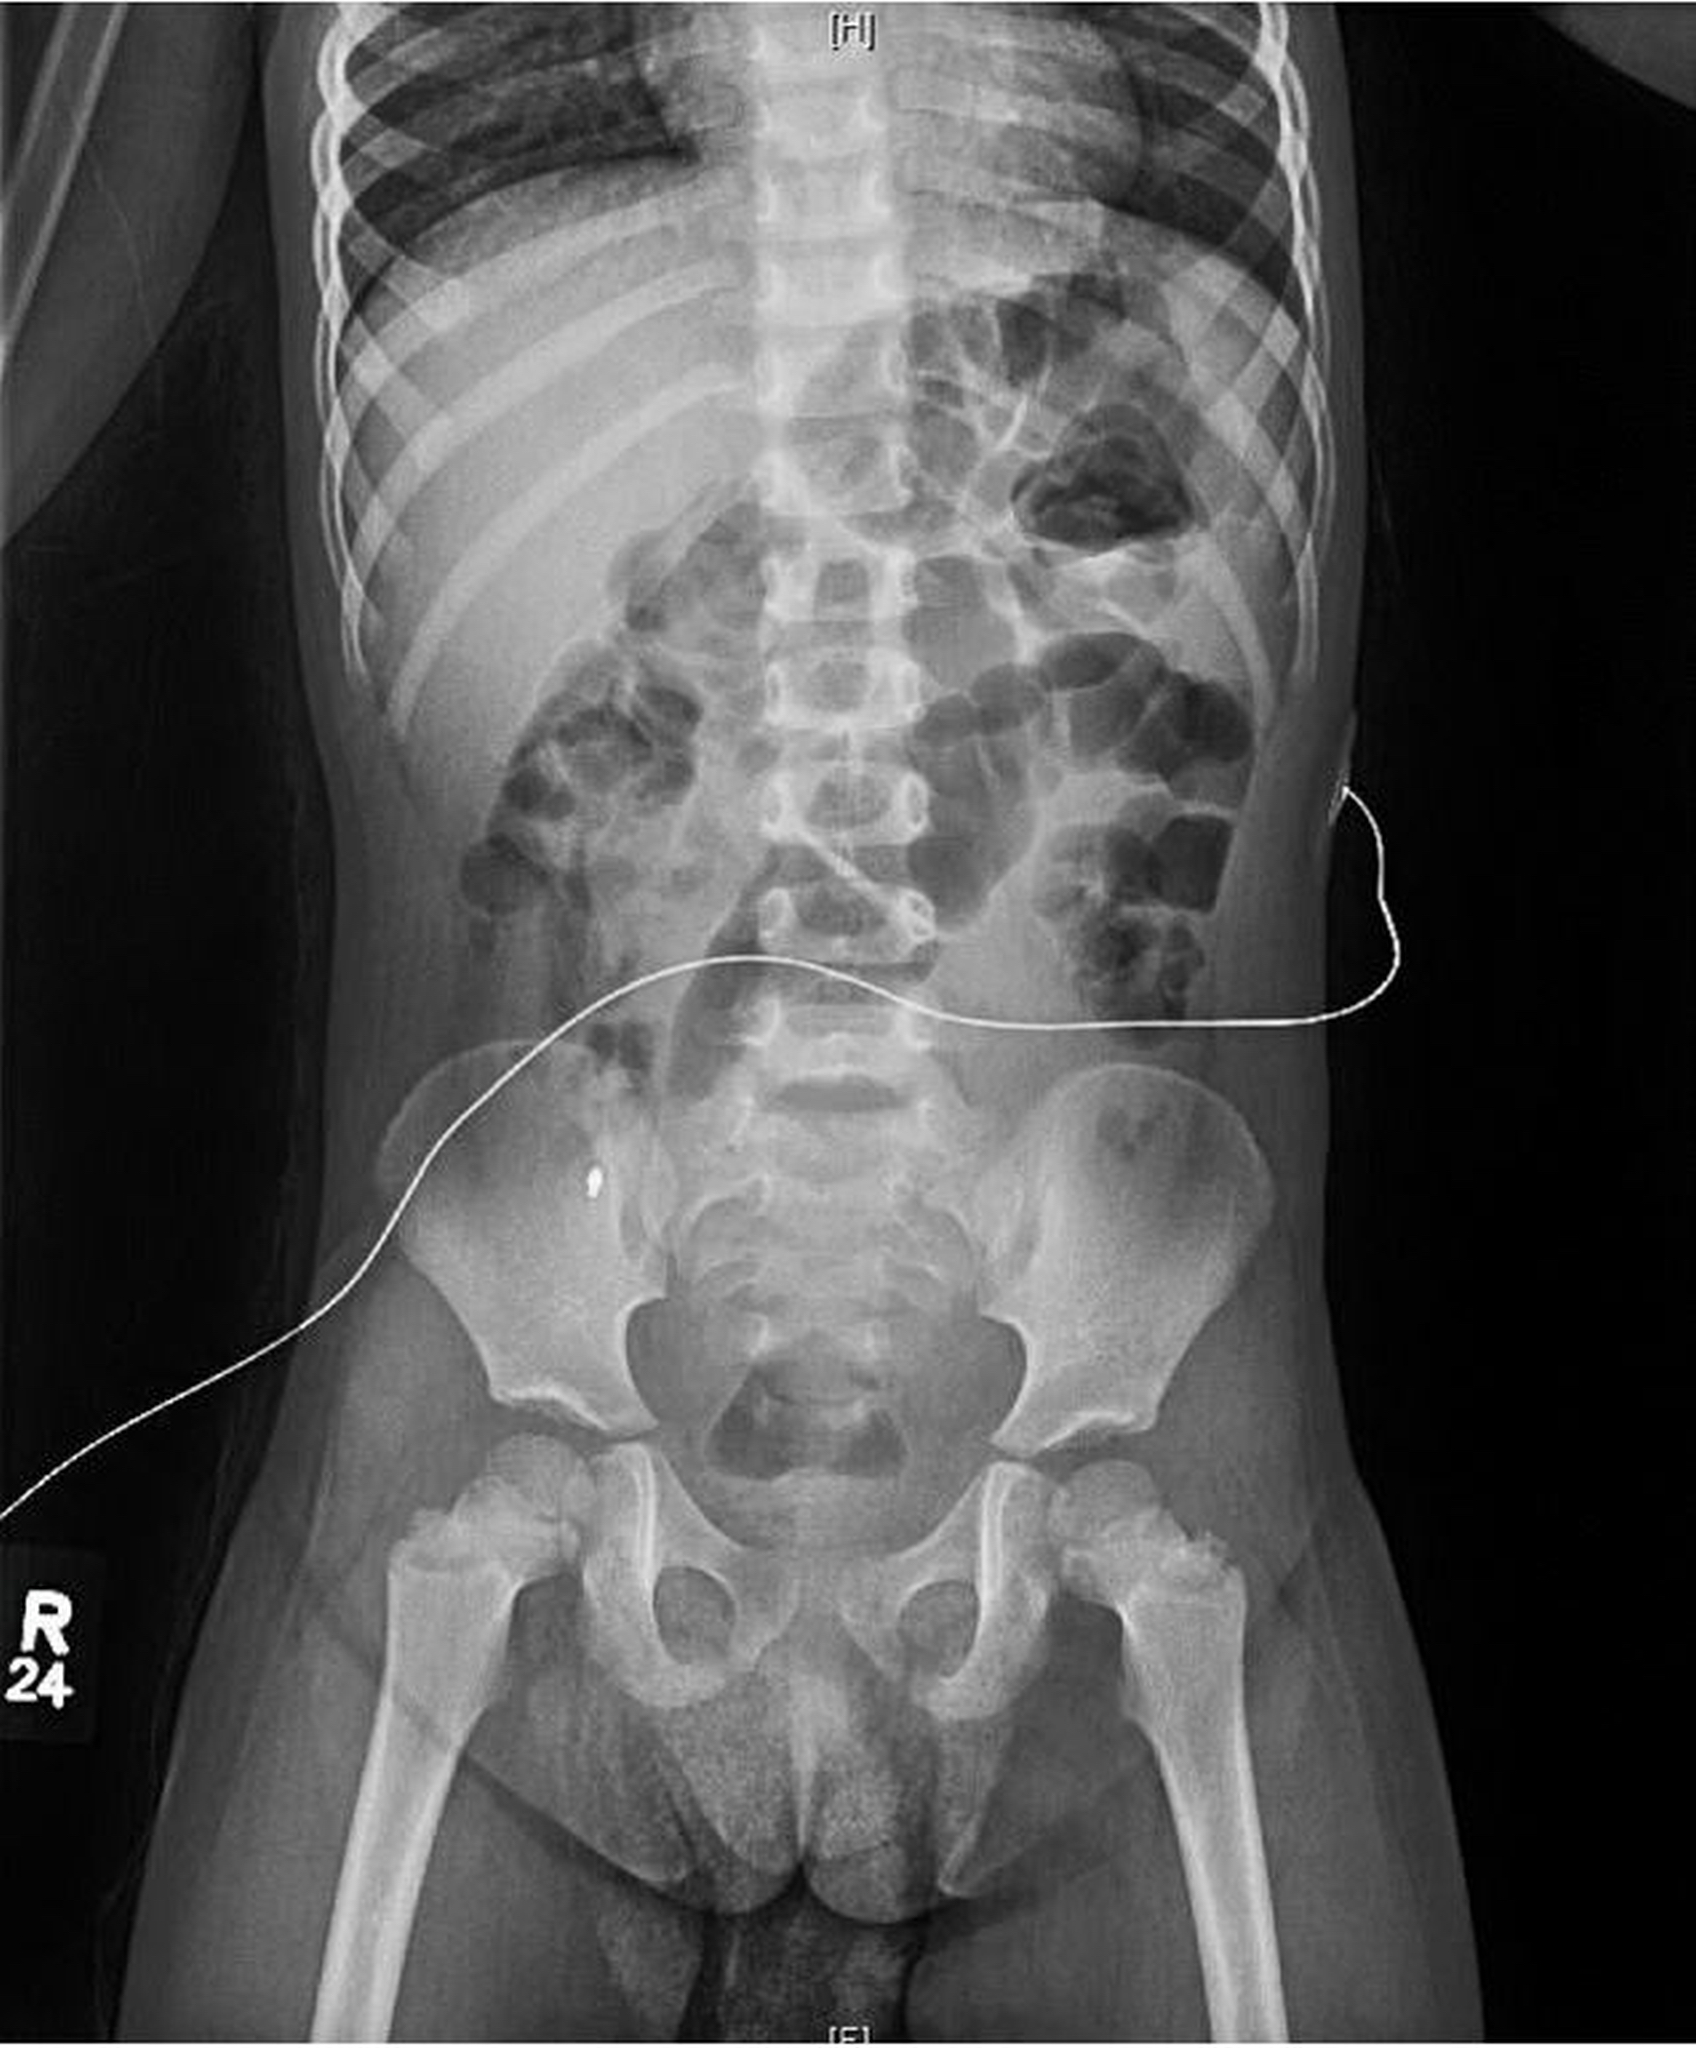

Due to concern about intermittent abdominal pain in the setting of the child found with knees to her chest, a limited abdominal ultrasonography scan was conducted, the findings of which indicated no element of intussusception. Plain radiography was performed to rule out stool burden, the findings of which incidentally showed a foreign body that appeared to be a pen tip in the right lower quadrant (Figure 1).

Figure 1. A plain radiograph showed a 2.9-mm metallic density over the right iliac wing.